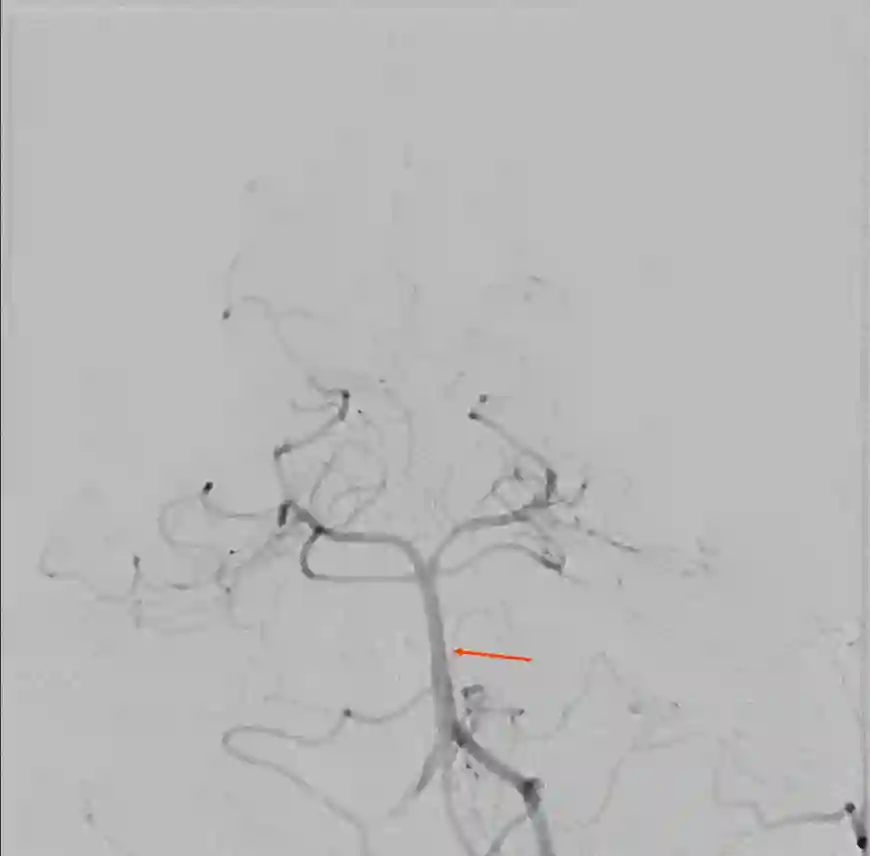

Basilarisspitzenaneurysma

Ein Basilarisspitzenaneurysma (roter Pfeil) in einer zerebralen Angiographie.